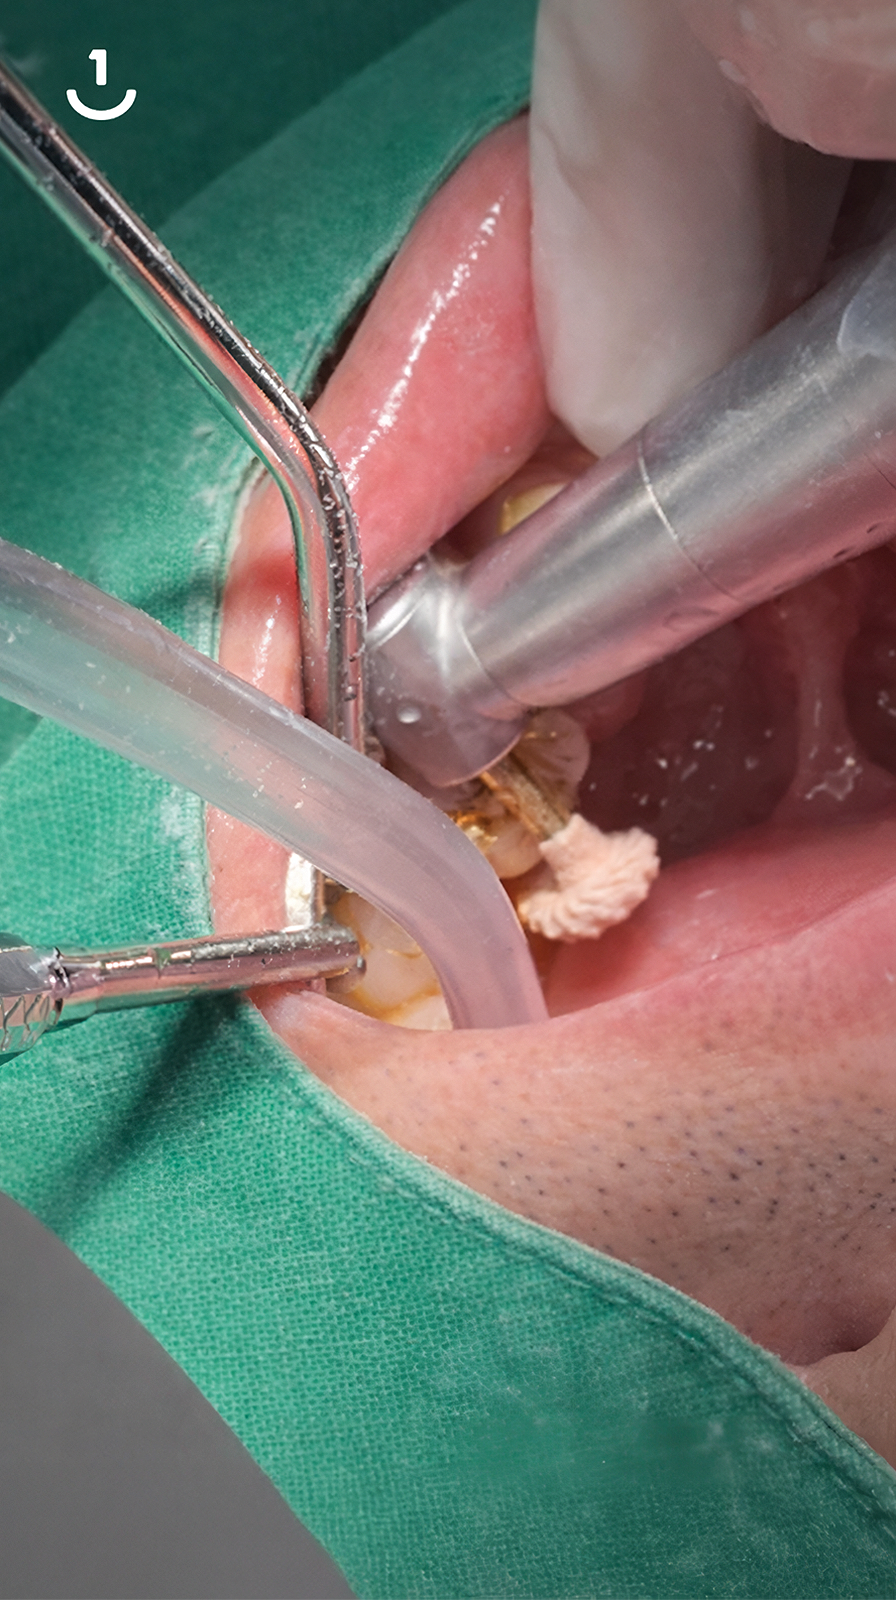

치과의사의 손길로 빚어내는, 섬세한 치아 수복

레진빌드업은 치과의사가 구강 내에서

직접 치아의 형태를 세심하게 만들어나가는 수복 방식입니다.

자연치아의 구조를 모방(biomimetic) 하여

신중하게 접착하는 과정을 거치며,

본래 치아와 조화롭게 기능할 수 있도록 돕습니다.